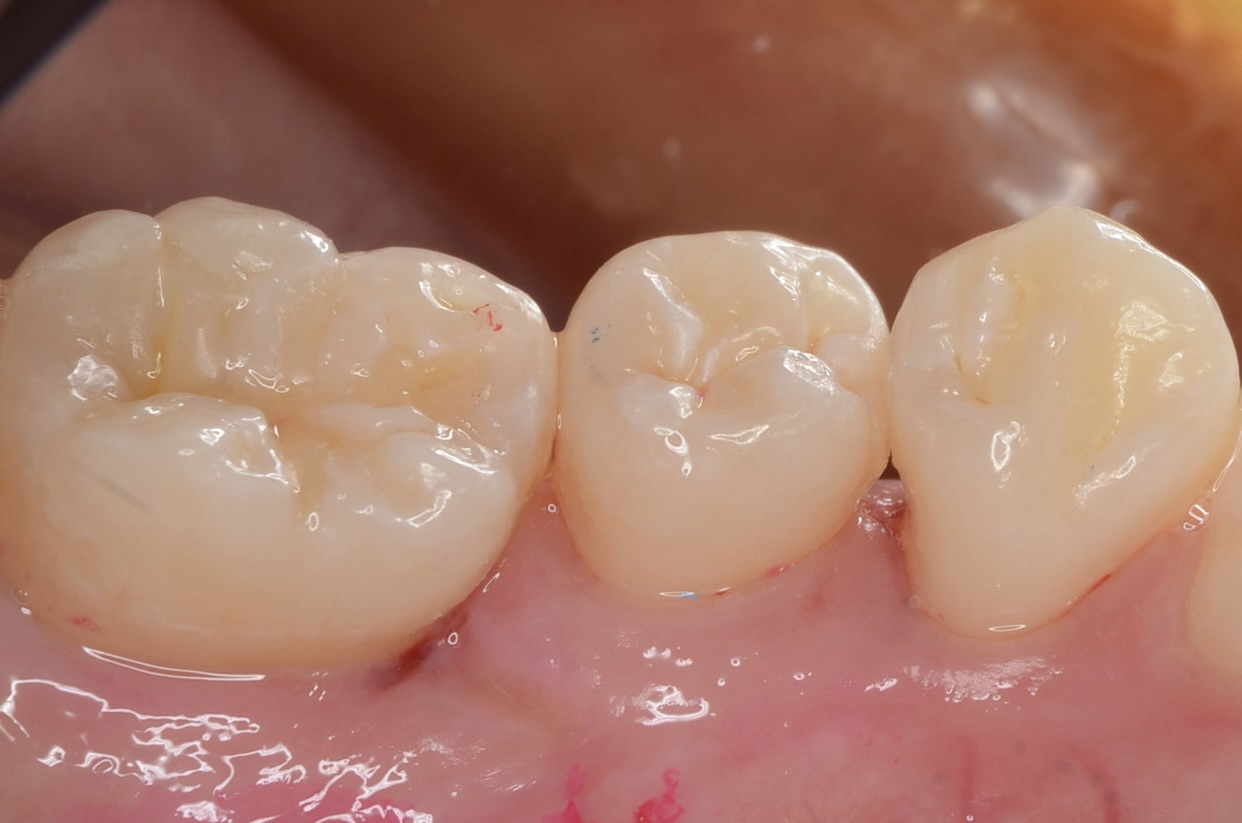

After

レジン充填完了

フロスを通してみて適切な、きつさがあるのを確認しています。 -

頬側面から見る

-

咬合面から見る

舌側面から見る

このように歯並びが若干乱れている場合の、歯と歯の間にできた虫歯治療は意外と難易度が高いです。しかしセパレーターを使って歯間離開させ、フロワブルレジンの表面張力を利用して充填すれば、滑らかで、引っ掛かりのない歯の形態を再現できます。